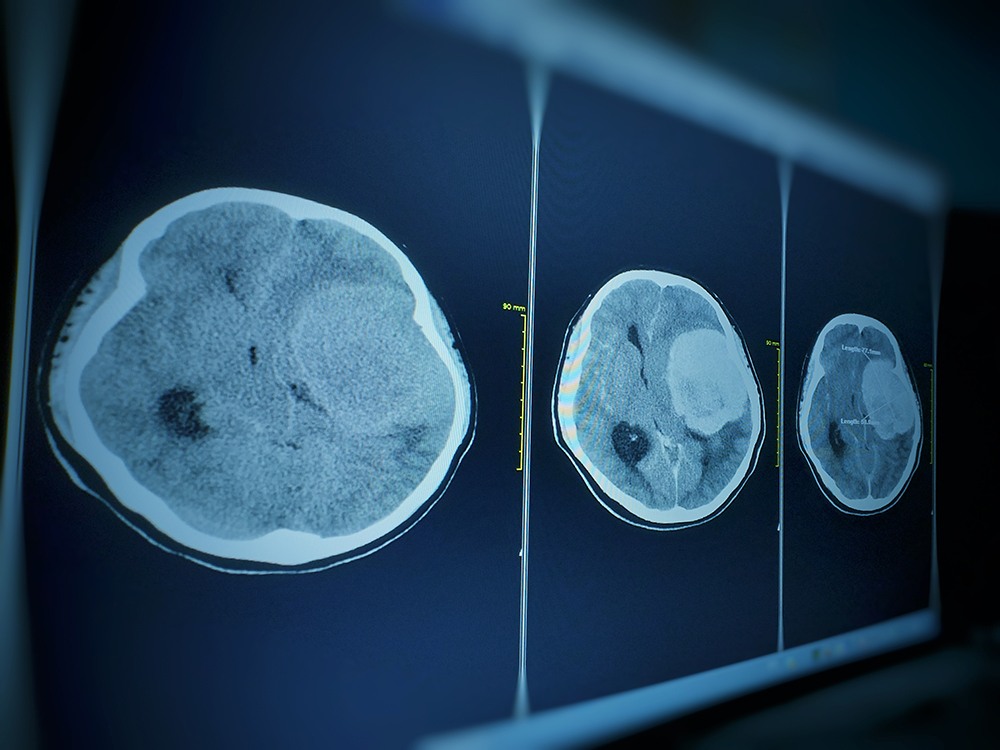

“That MRI showed an approximately two and a half by two centimeters, extra-axial brain tumor situated at the tuberculum sellae, which is a very common location for meningiomas,” explained Dr. Daniel F. Kelly, Director and one of the founders of PNI.

In this particular case, the meningioma was located in the patient’s left optic canal, causing progressive vision loss. Dr. Kelly and Dr. Chester F. Griffiths, Director of the Eye, Ear & Skull Base Center and Co-Founder of PNI, used minimally invasive surgery to remove the tumor.